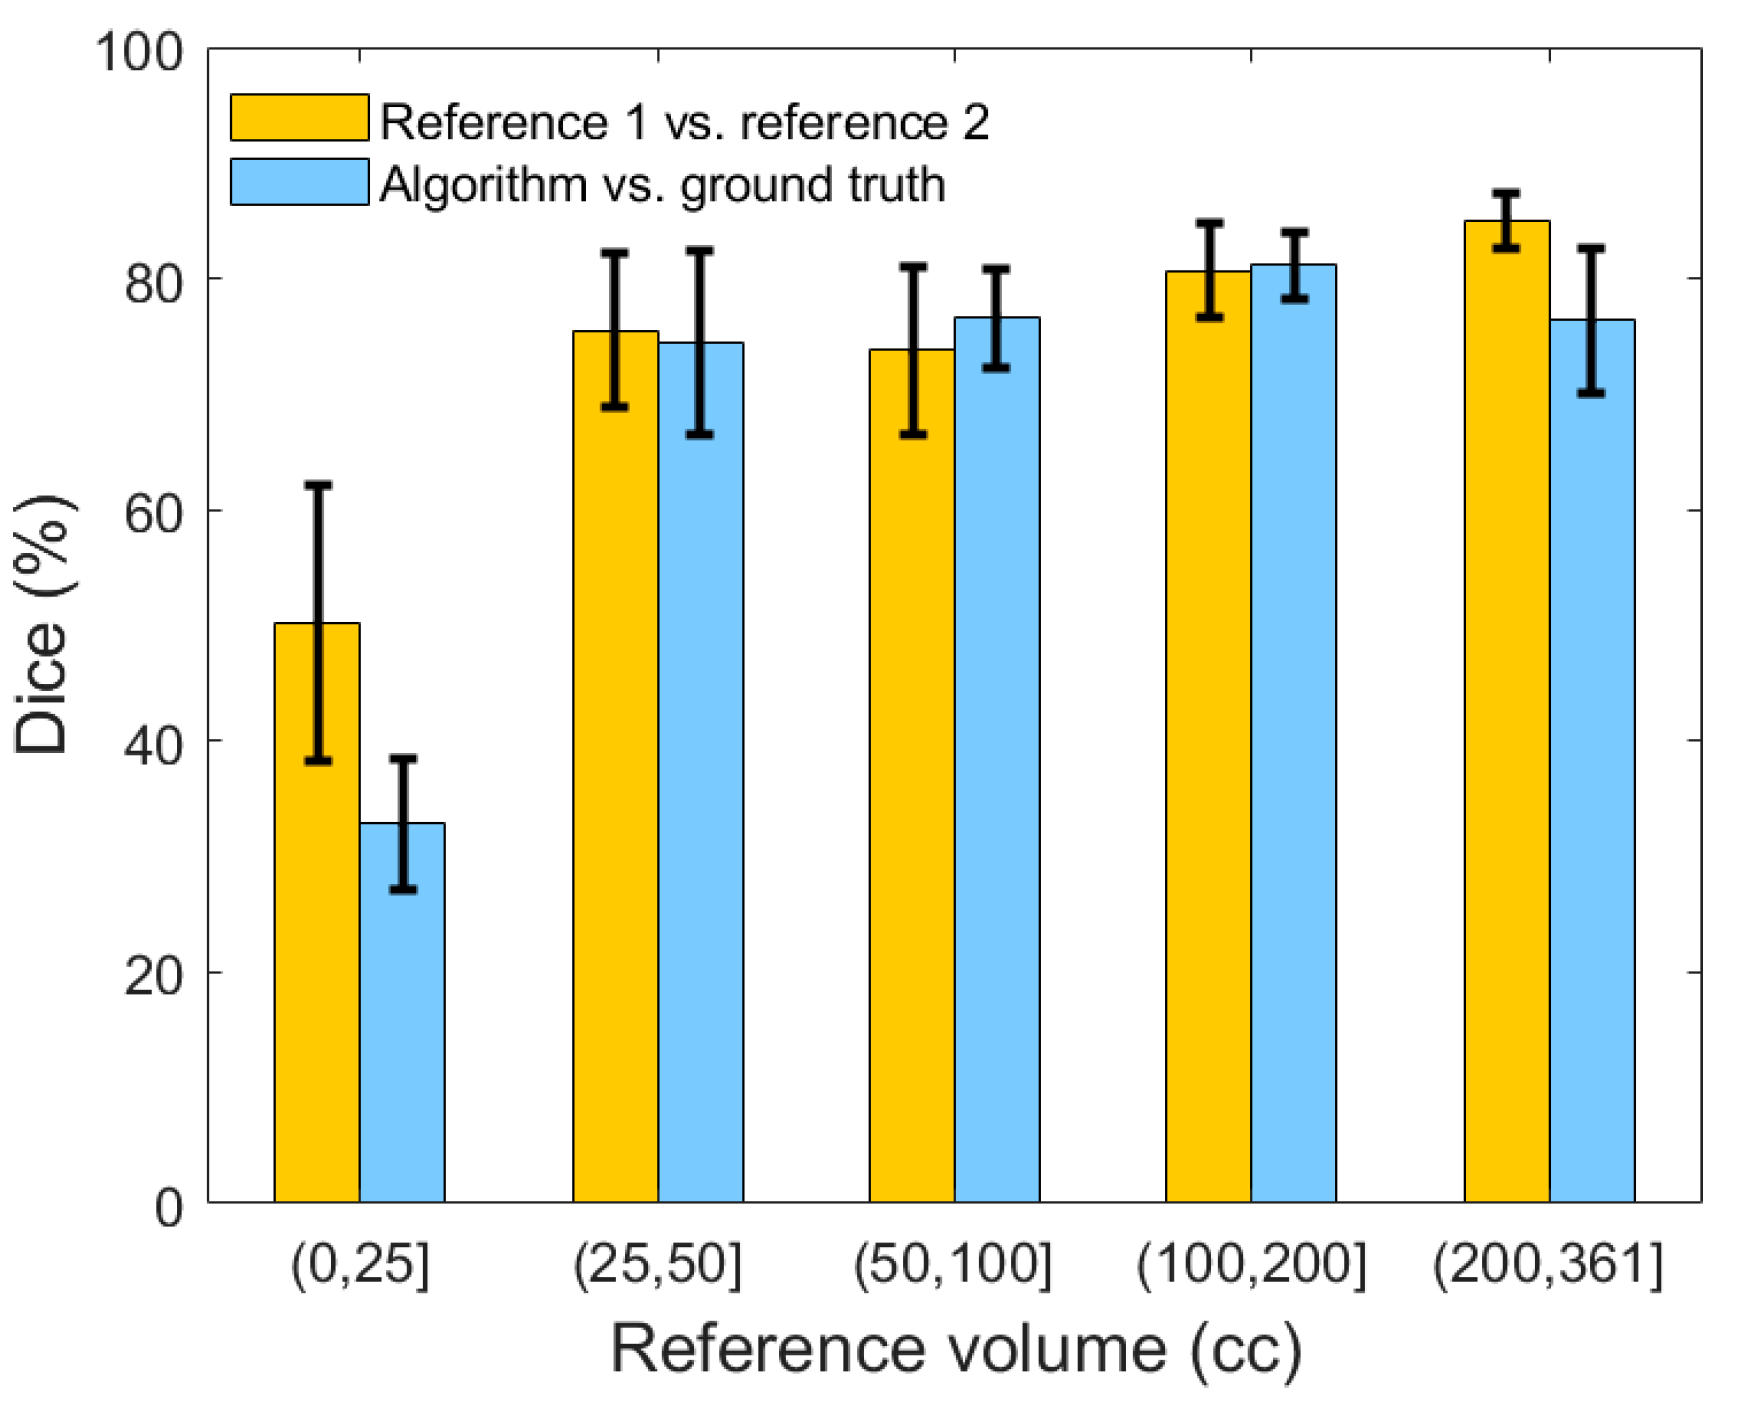

4.4. Inter-Physician Variability Analysis

Figure 11 illustrates the comparison between the two neuroradiologists, as well as a comparison of our algorithm’s segmentation against the adjudicated ground truth with respect to the selected 20 patients. The average inter-rater Dice similarity coefficient on the selected subset of 20 SDH CT scans is 73.71%, while this coefficient is 50.20% and 77.85%, respectively, when stratifying lesions based on <25 cc and ≥25 cc of blood. On the same subset, the algorithm′s average Dice similarity coefficient value reached 77.81% for moderate and severe SDHs compared to 77.85% for human raters.

Figure 11.

Comparison of the Dice similarity coefficient between reference 1, reference 2, and the result of our segmentation algorithm. Error bars represent ±1 standard errors, the 68% confidence interval.

Figure 11.